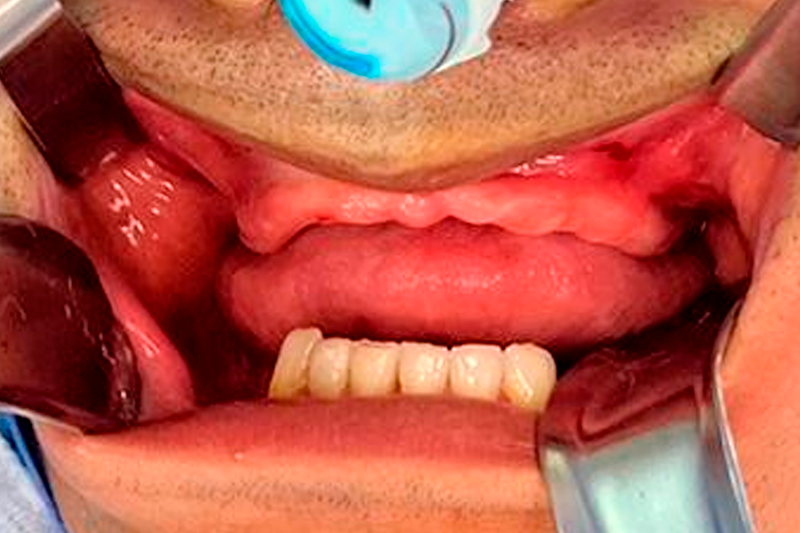

CUSTOMLIFE NA PRÁTICA

Confira case cirúrgico

Reconstrução de Maxila Total